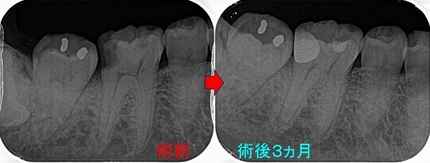

レントゲン

2026 EEdental NNS (1).jpg

口腔内写真

2026 EEdental NNS (2).jpg

低目にレジンが詰めてあります。

患者さんには咬頭が無くなっており、中で虫歯もひろがっていそうだから

メタルアンレーで治しましょうと説明

2026 EEdental NNS (3).jpg

術前⇒術後

2026 EEdental NNS (5).jpg

2026 EEdental NNS (4).jpg